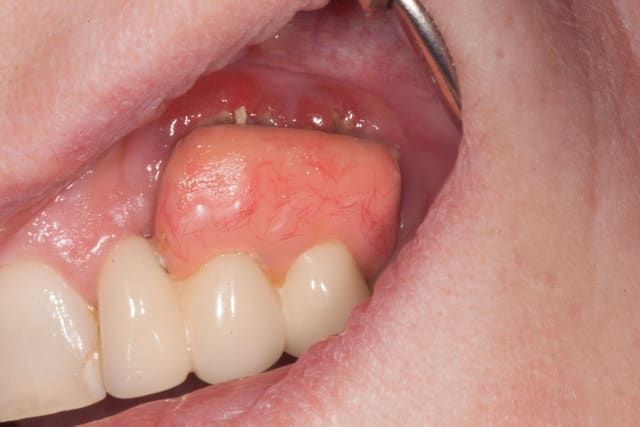

Cliniquement, si la 22 a été réalisée de façon classique, 23 et 24 sont montée sur une armature métallique en selle. En palatin, la selle avance sur le palais de 2 mm, mais en vestibulaire, on est plus à 8 mm de recouvrement.

La formation de tartre dans l'intrados de la selle donne une gencive inflammatoire, saignant spontanément au passage d'un fouloir rond. Je vous laisse voir les photos.